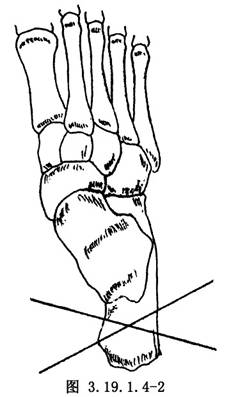

(2)足跟部件的安裝:在垂直於跟骨矢狀面的平面上,靠近跟骨結節的部位經皮鑽入兩枚交叉克氏針(直徑1.0~2.0mm,交叉角度40°~60°)(圖3.19.1.4-2),將2枚克氏針的內外側端分別固定在一個半環部件上。